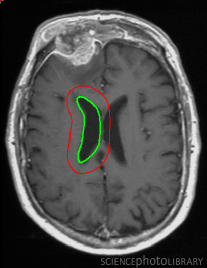

Figure 12: Segmentation of corpus callosum images in sagittal plane T1-weighted brain magnetic resonance images taken from [37]. For all images, the same template was used and initialized in a manner similar to the way shown in the top left corner image. The converged results using the proposed shape template approach and the result obtained on subsequent refinement using snake energies[22] are displayed alongside.

In Figure 12, we show the results obtained for segmentation of corpus callosum in T1-weighted MR images. Many techniques on segmentation of corpus callosum are affected by the adjoining fornix structure due to the similarity in intensities. However, it can be observed from the results that the proposed snake is less affected by the fornix. We further refine results obtained using the proposed technique with gradient energies[22]. We display the results obtained on refinement alongside the output from the proposed shape-based approach.